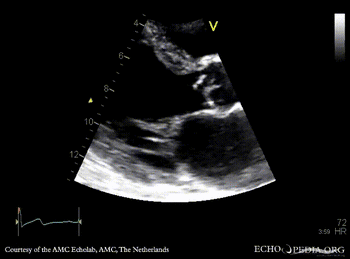

Endocarditis of aortic valve

PSAX: thickend aortic valve M-Mode: dilated left ventricle